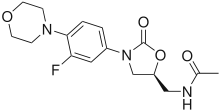

- ... vinca alkaloids are chemotherapy drugs that inhibit the polymerization of tubulin, whereas taxanes are produced by plants of the genus Taxus that inhibit tubulin depolymerization?